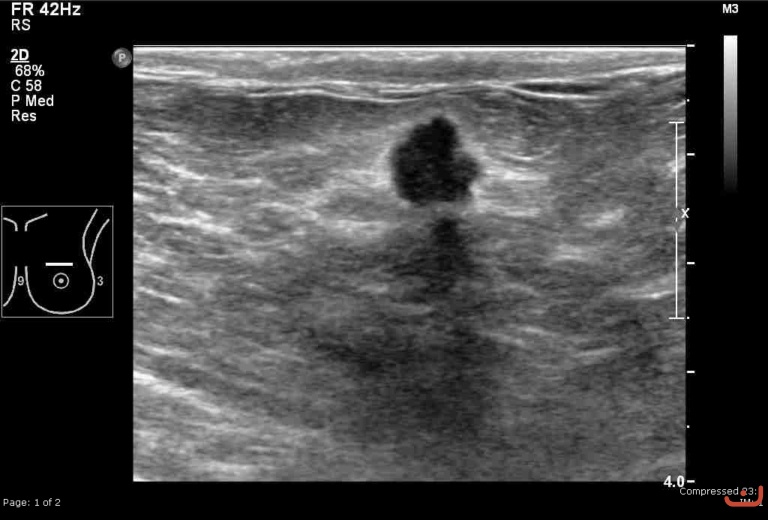

Malignant solid mass

Thursday, 30 April 2015

176.57 KB (768 x 520 px)